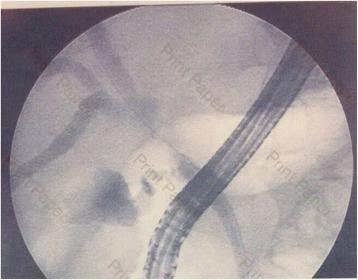

We report the case of a 56-year-old man who presented with obstructive jaundice with preoperative imaging showing proximal common bile duct obstruction. He underwent right lobe liver hepatectomy with extrahepatic bile duct resection and regional lymph node dissection due to high suspicion of malignancy. The pathological report showed severe acute and chronic inflammation of the bile duct with morphology and immunohistochemistry suggestive of IgG4-related sclerosing cholangitis.

我们报告一例56岁男性患者,因梗阻性黄疸就诊,术前影像学检查显示肝总管近端梗阻。因高度怀疑恶性肿瘤,患者接受了右半肝肝切除术、肝外胆管切除术及区域淋巴结清扫术。病理报告显示胆管存在严重的急慢性炎症,形态学及免疫组化结果提示为IgG4相关硬化性胆管炎。